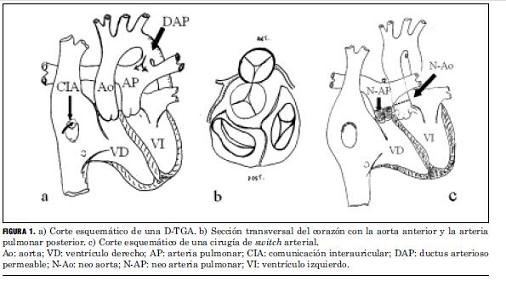

Se analizó una población de 60 pacientes (de un total de 62) portadores de una D-TGA que fueron dados de alta luego de ser sometidos a cirugía de switch arterial en nuestra institución durante el primer mes de vida, dos pacientes no fueron localizados. Esta experiencia abarca el período 1994-2005 (figura 1).

El análisis anatómico destaca que 40 pacientes presentaron D-TGA con séptum interventricular intacto y 20 con comunicación interventricular. Uno de estos pacientes asoció una coartación de aorta con severa hipoplasia del arco aórtico, otro era portador de un situs inversus (figuras 2 y 3), y otro presentaba una estenosis subpulmonar leve (tabla 4, figura 4).

La reparación quirúrgica se llevó a cabo con circulación extracorpórea e hipotermia profunda, realizando translocación de las arterias coronarias mediante la creación de un flap en la neoaorta (incisión de trap-door) para evitar distorsión de las mismas, maniobra de Lecompte con disección de las ramas pulmonares hasta los hilios, conexión directa de la neoaorta con la aorta distal y parche de pericardio autólogo fijado en glutaraldehído para la reconstrucción de la arteria pulmonar.